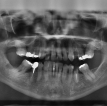

Revolucija v zobozdravstvu: Ljudem bodo lahko zrasli novi zobje namesto zalivk

Zahvaljujoč znanstvenemu odkritju na področju regenerativne medicine bi odraslim v prihodnosti lahko zrasli novi zobje namesto uporabe zalivk ali vsadkov. Ta inovacija odpira vrata naravni alternativi pri zdravljenju zob.

Medtem ko lahko nekatere živali, kot so morski psi in sloni, regenerirajo zobe vse življenje, ljudje v odrasli dobi ostanejo samo z enim nizom zob. Nova tehnologija, razvita na King's College London, bi lahko to za vedno spremenila.

Za razliko od zalivk in vsadkov, ki so umetni in podvrženi razpadu, se lahko zobje, vzgojeni v laboratoriju iz pacientovih lastnih celic, naravno vključijo v čeljust in se obnašajo kot pravi zobje – močnejši, dolgotrajnejši in brez nevarnosti zavrnitve.